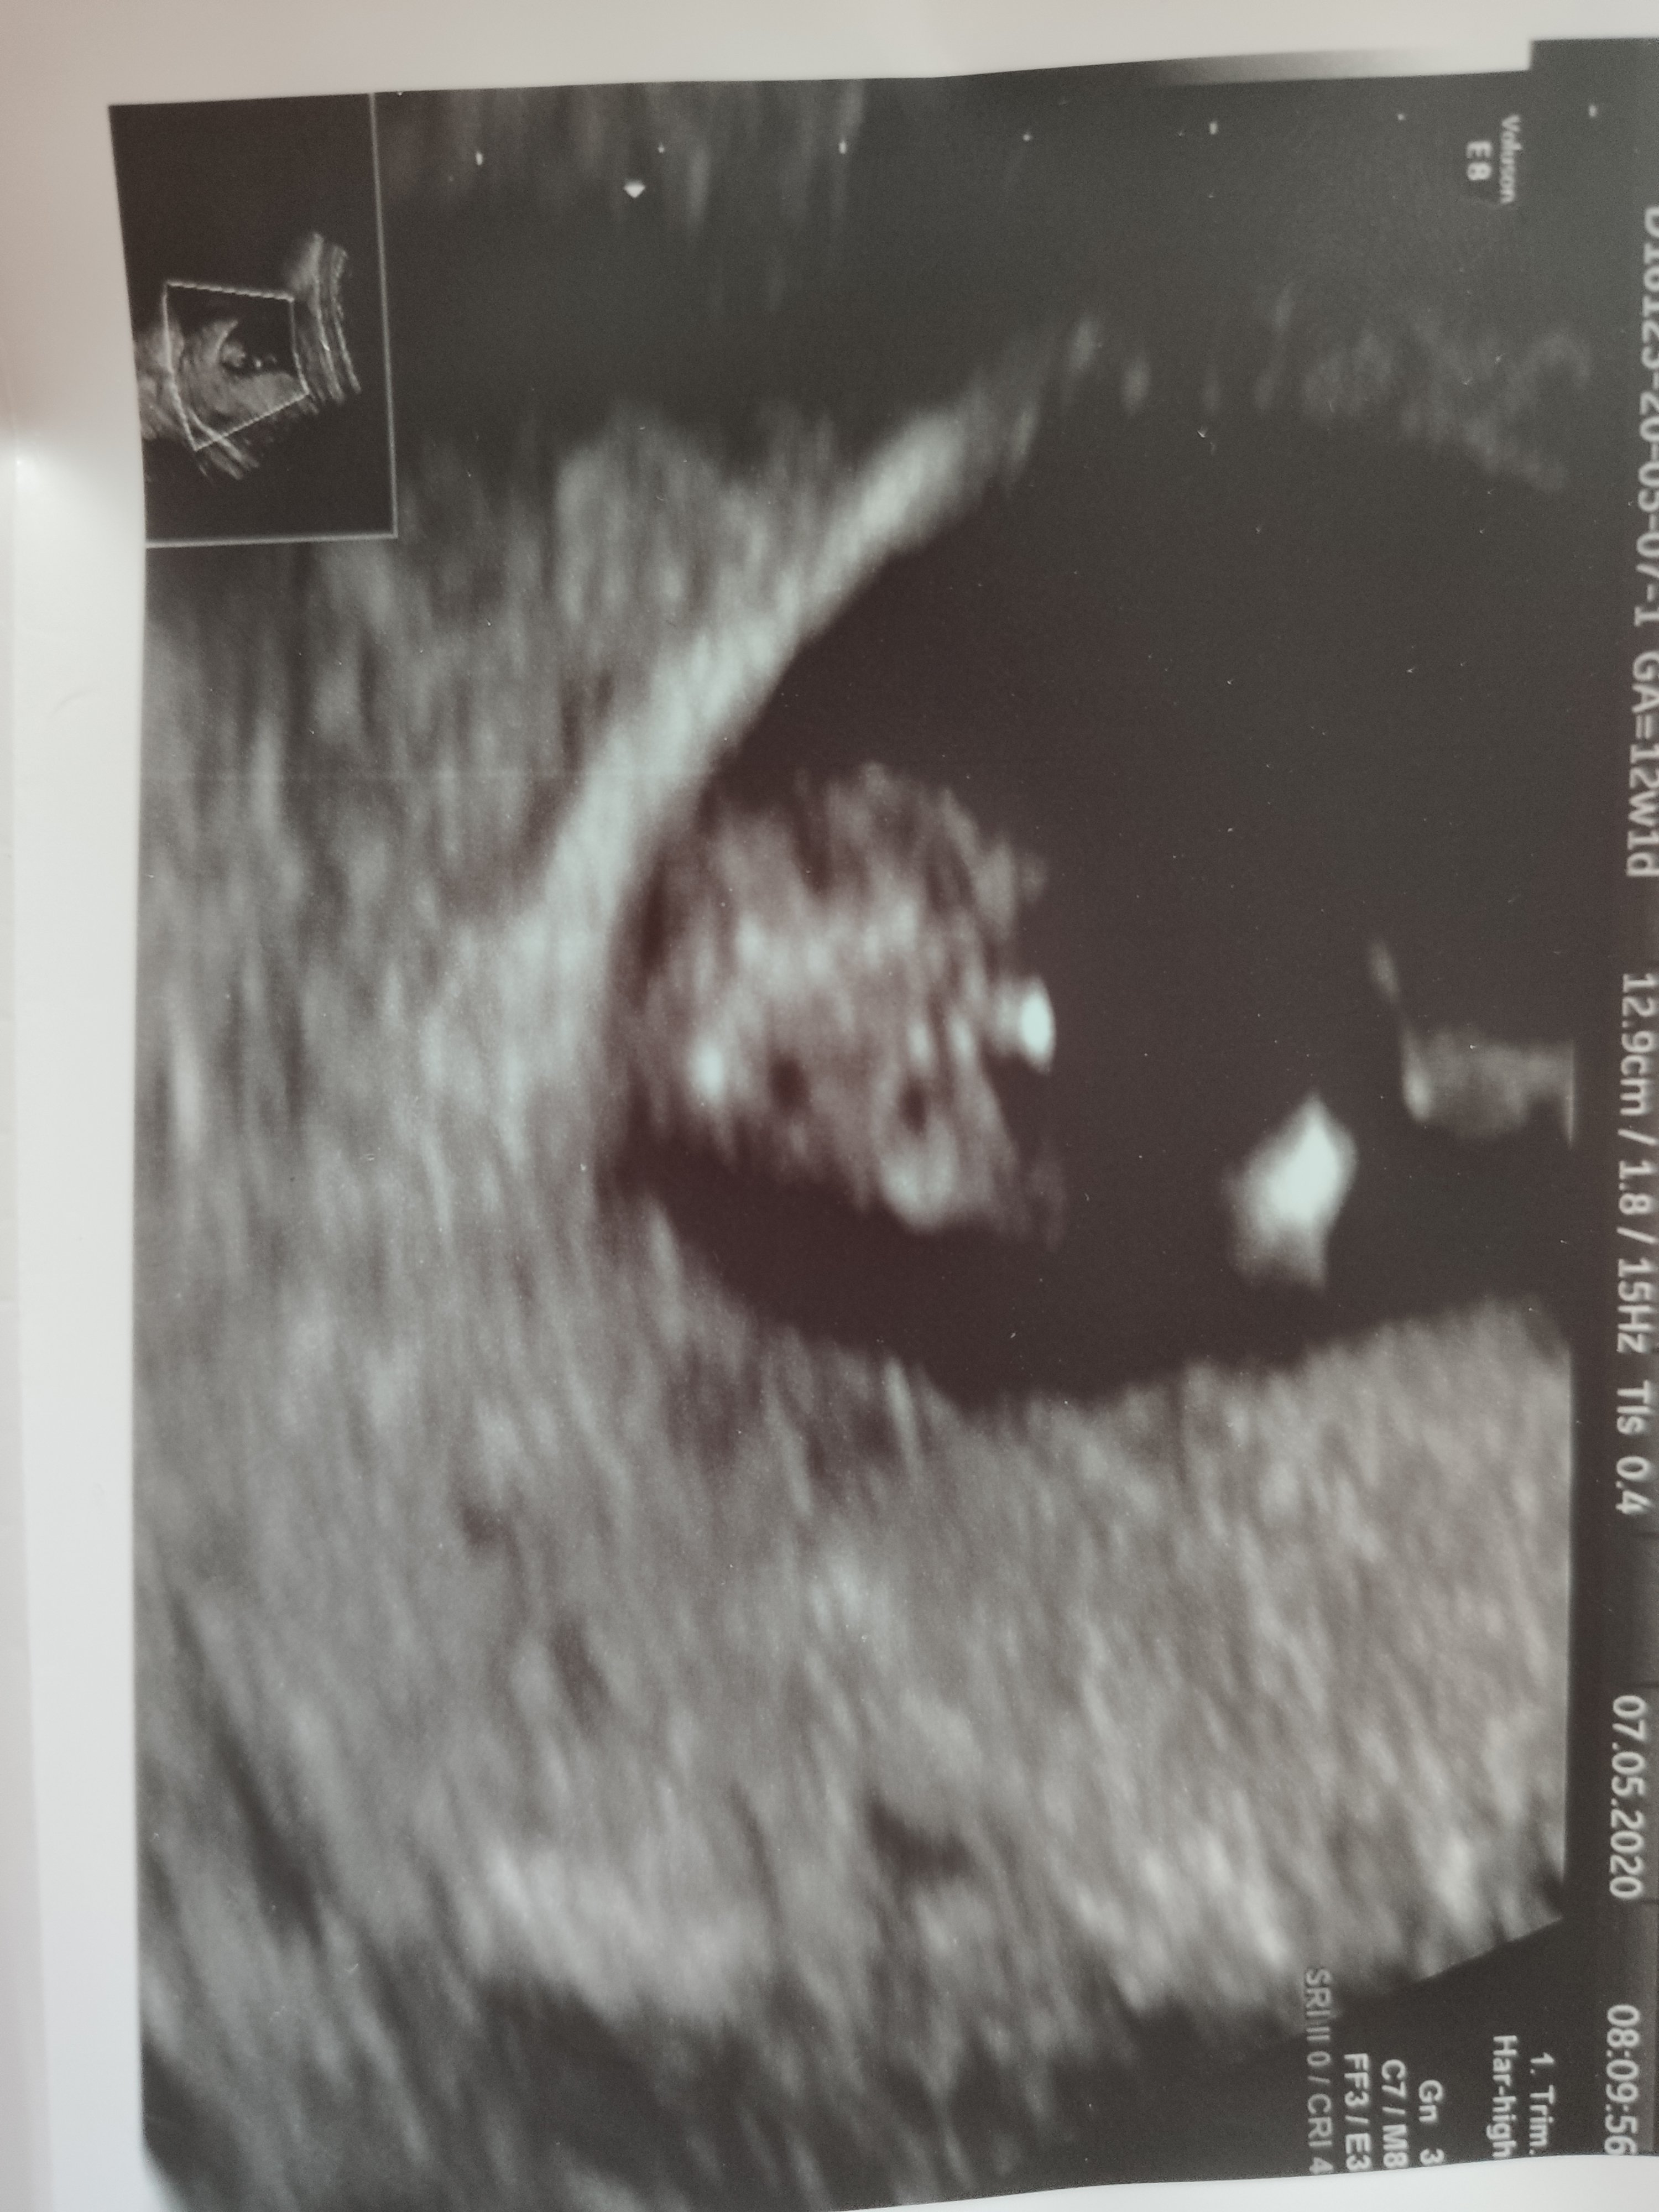

Hej 😊

u mnie pare miesięcy temu sprawdziła się opinia z tego wątku 🥰 może z koleżanki zdjęć tez da się ocenić jakiej płci jest dzidzia? 🍀

Załączniki

• 27786919-3188-4B8D-90EF-8099EB91E856.jpeg

27786919-3188-4B8D-90EF-8099EB91E856.jpeg

285,7 KB · Wyświetleń: 181

• 7F492542-0701-4E7B-8691-508FEFB89896.jpeg

7F492542-0701-4E7B-8691-508FEFB89896.jpeg

348,3 KB · Wyświetleń: 184